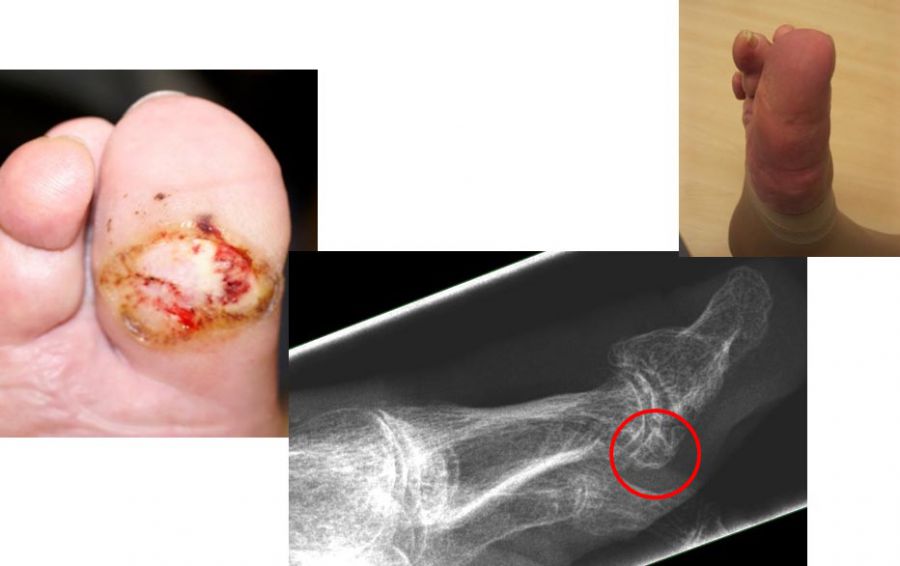

Chronische Ulcera führen längerfristig zu einer oberflächlichen Infektion des Fußes. Über die Zeit kann sich die Infektion in tiefere Gewebsschichten ausbreiten und den Knochen befallen. Bei einem ungünstigen Verlauf kann der Fuß so stark geschädigt werden, dass eine Amputation nicht mehr zu vermeiden ist. Neben einer schlechten Durchblutung und einer verminderten Gefühlswahrnehmung des Fußes (Polyneuropathie) führen häufig mechanische Druckstellen durch Knochenkanten zu Hautschäden. Um frühzeitig die Entstehung von Hautläsionen zu vermeiden, können wird häufig empfohlen störende Knochenkanten durch kleine operative Eingriffe abzutragen, bevor es zu einer Druckstelle kommt.

- Operative Behandlung von Druckstellen durch Hallux valgus

Aufgrund einer Fehlstellung der Großzehe nach außen (Hallux valgus) kann es zu Druckstellen bzw. Hautläsionen zwischen der 1. und 2. Zehe sowie kommen. Gefährdet ist auch die Haut auf der Innenseite des Fußes über dem Großzehengrundgelenk. Sollten hier konservative Therapiemaßnahmen (Polsterung/Schuhzurichtung) versagen, ist eine operative Korrektur des Hallux valgus anzuraten. - Operative Behandlung von Druckstellen durch Hammerzehen

Bei Hallerzehenfehlstellung kann es zu Druckstellen bzw. Hautschäden an der Zehenspitze oder über dem Zehenmittelgelenk kommen.Sollten hier konservative Therapiemaßnahmen (Polsterung/Schuhzurichtung) versagen, ist eine operative Korrektur der Hammerzehe sinnvoll, bevor offene Stellen entstehen, die dann zu Eintrittspforten für Keime werden.

- Operative Behandlung von Druckstellen durch Knochenvorsprünge (Exostose)

Im Bereich des Fußes können an verschiedenen Stellen Knochenanbauten (Exostosen) z.B. im Rahmen von Arthrose zu Druckstellen und dann zu Hautschäden führen. Hier ist die prophylaktische Abtragung des Knochenüberstandes sinnvoll. Immer wieder verhindern auch Knochenkanten die Heilung einer schon vorhandenen Hautwunde. In vielen Fällen lassen sich heute solche Knochenkannten minimalinvasiv in der sog. „Schlüssellochtechnik“ ohne große Operation entfernen.

Zum Lesen der Bildbeschreibung und Vollansicht bitte Bild anklicken. Fotos: Alexander Mehlhorn